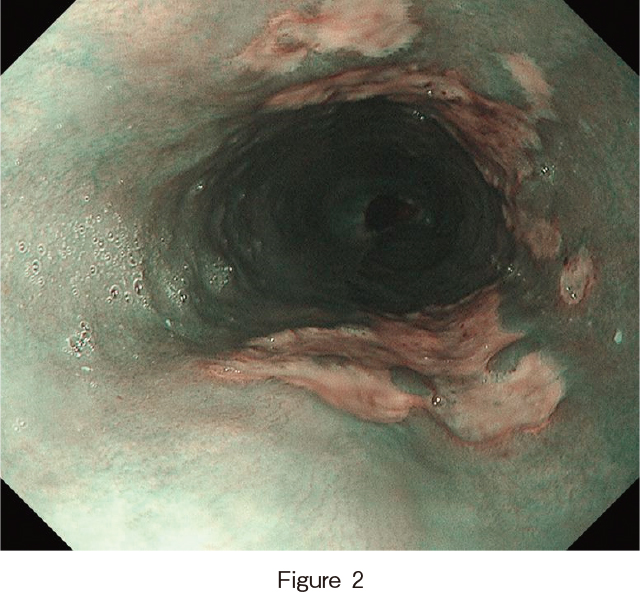

上部消化管内視鏡所見(入院翌日):胸部中部食道に辺縁明瞭な地図状潰瘍を認め,潰瘍は腹側と背側に多発していた(Figure 1,2).

通常光観察では,中部食道に辺縁明瞭な大小不同の不整形潰瘍が背側・腹側に多発している.

狭帯域光観察では,潰瘍辺縁粘膜の表面に明らかな粘膜構造および血管構造の不整は認めなかった.